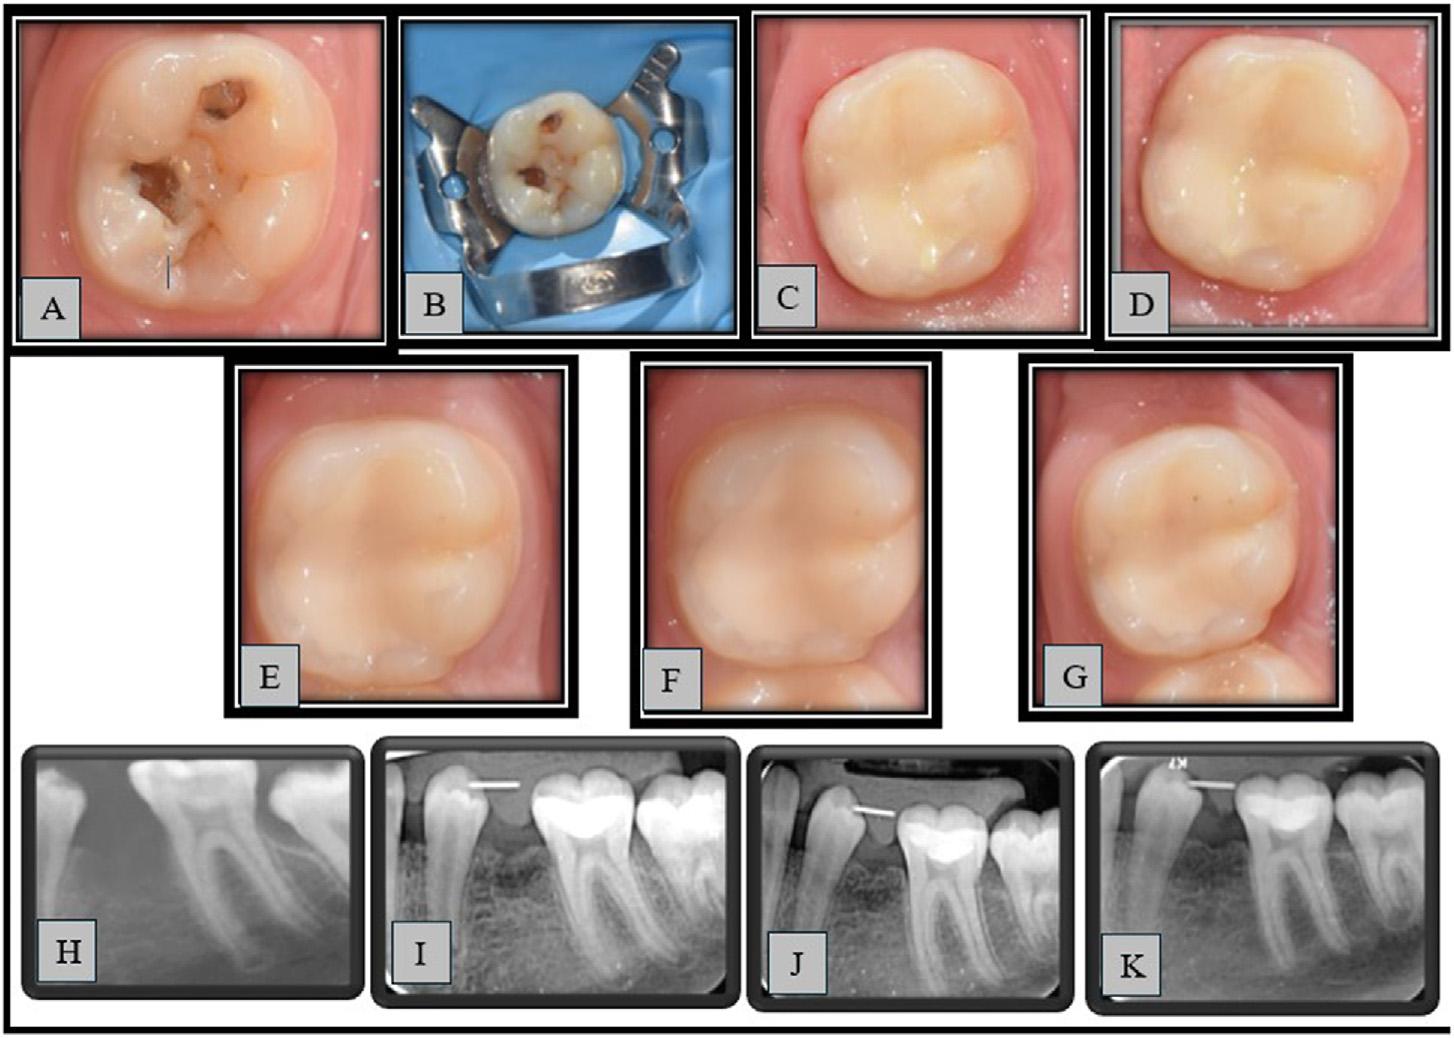

SilverDiamineFluorideforIndirectPulpCappingof theFirstPermanentMolar

IndirectPulpCappingforSevereEarlyChildhood CariesLesions